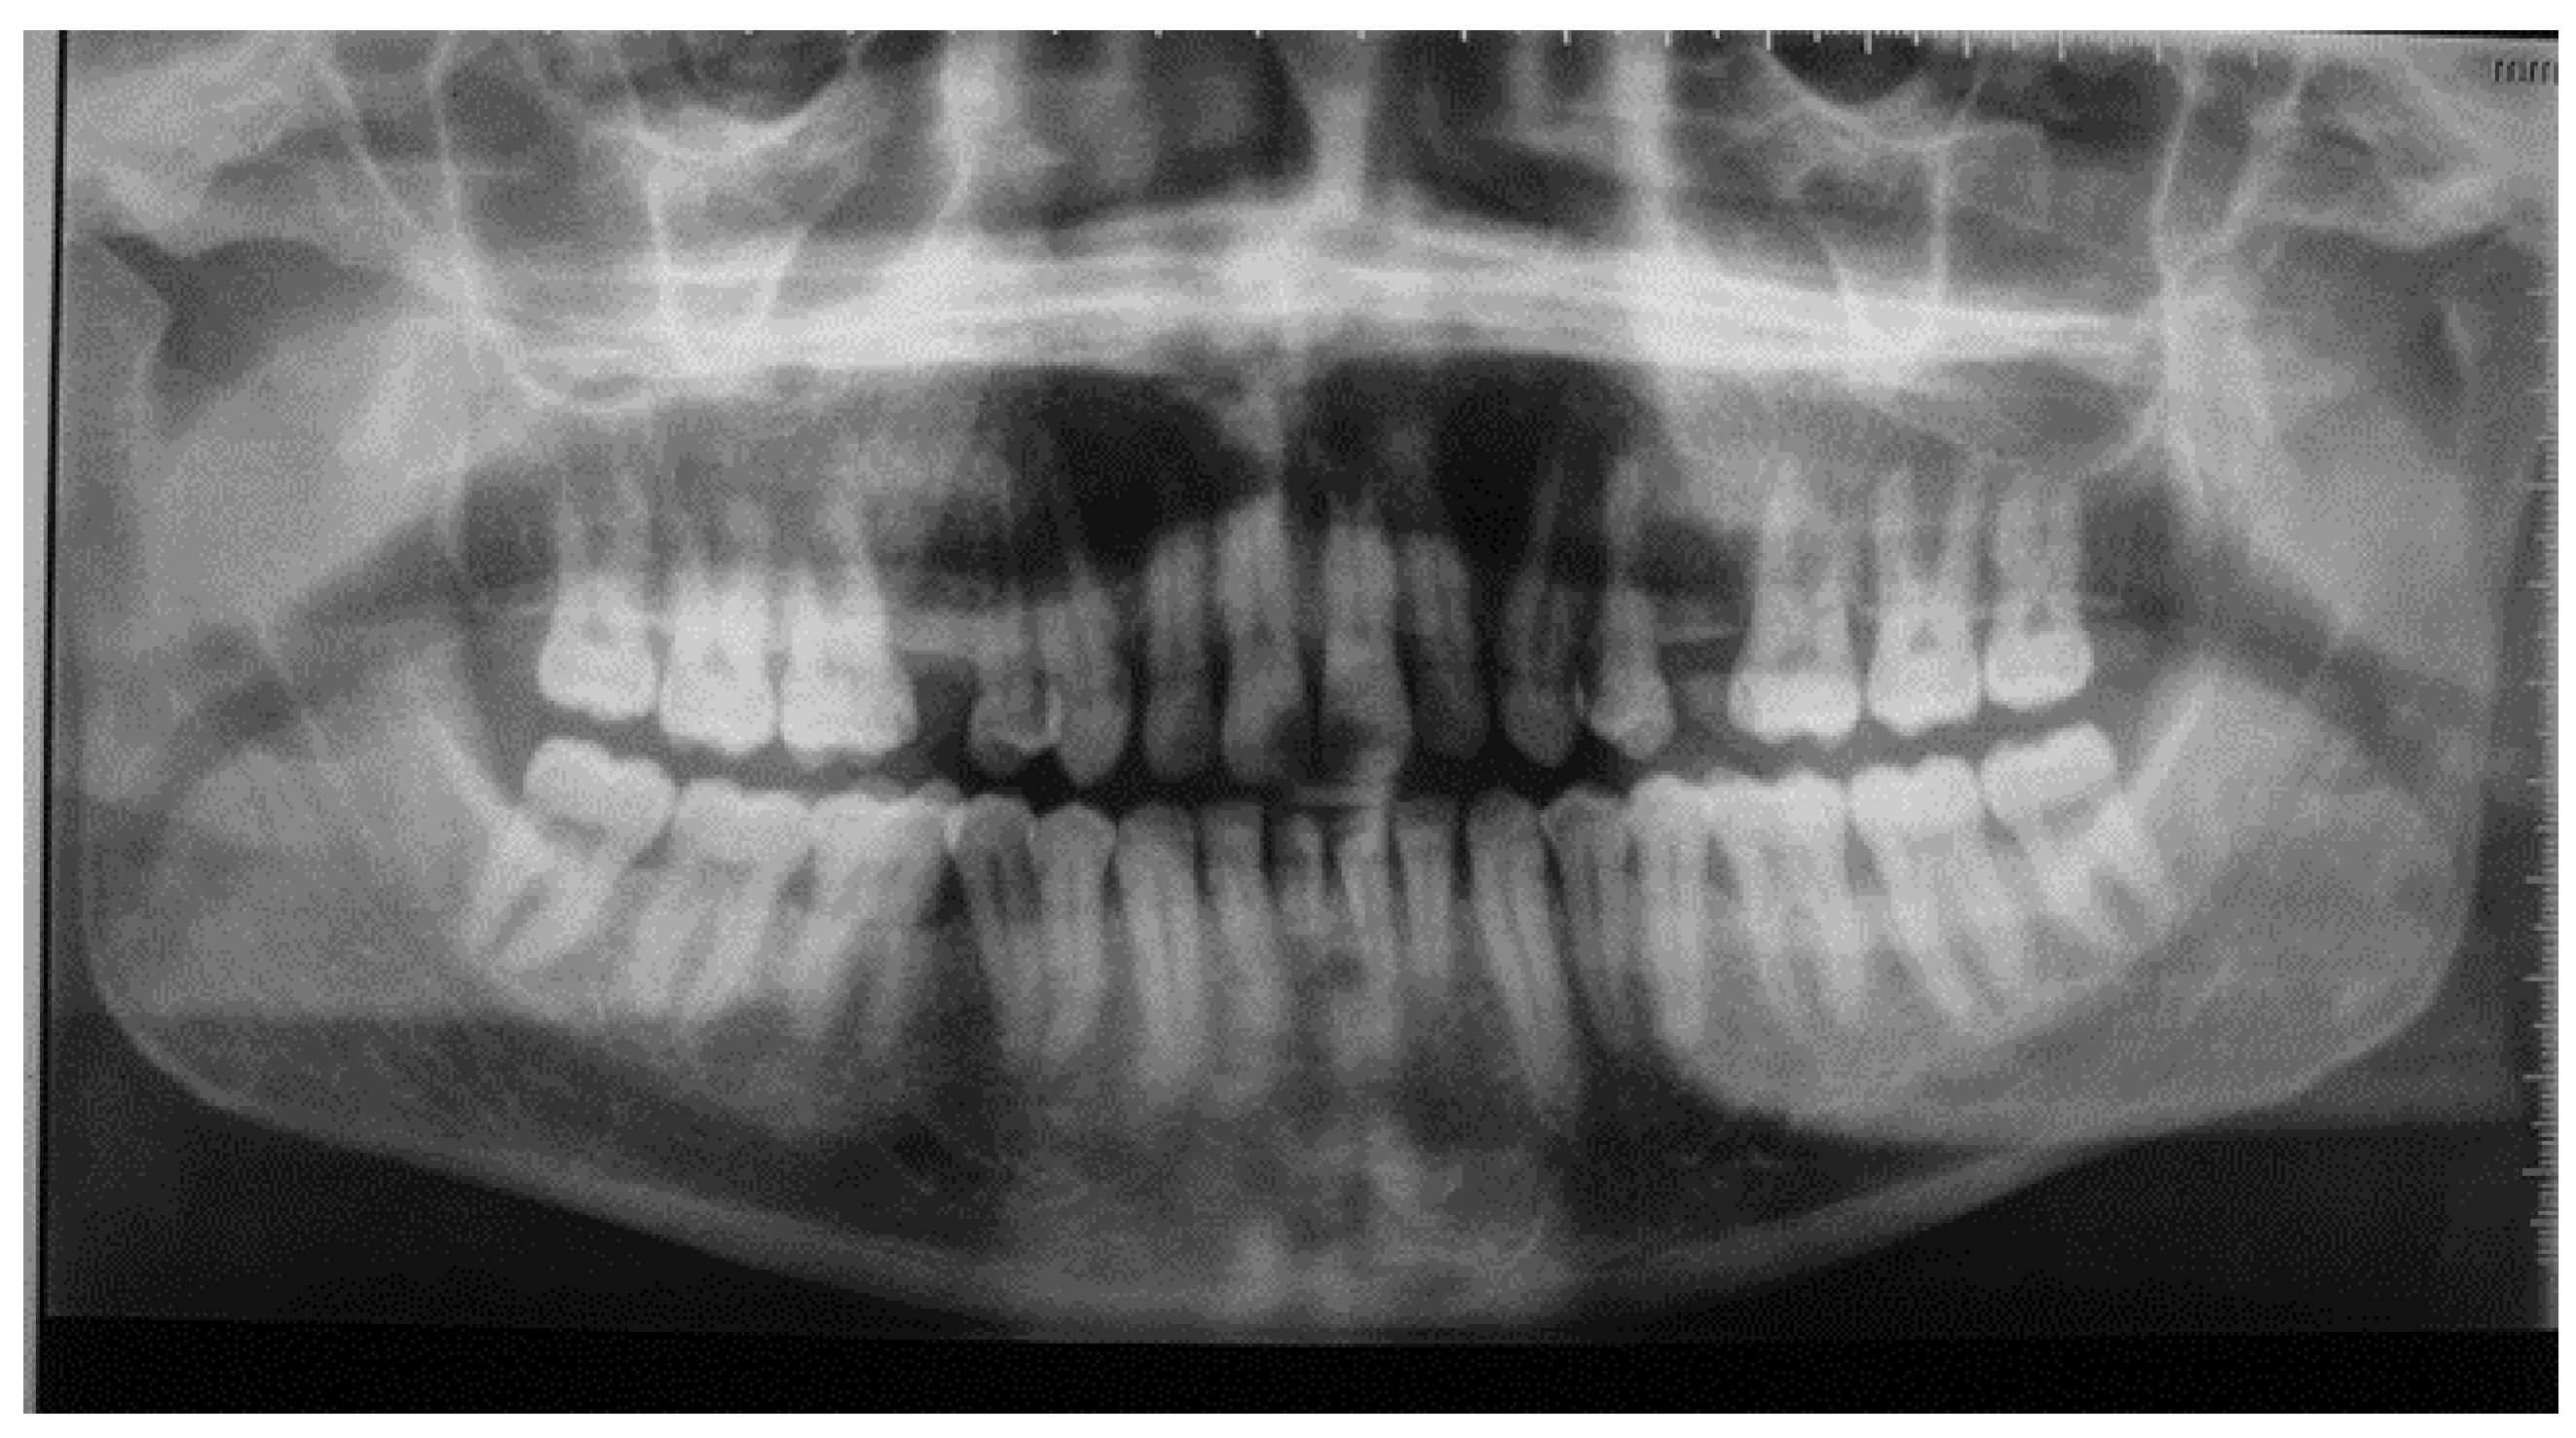

Radiographic examination showed horizontal bone lysis affecting approximately two-thirds of the roots of the teeth, consistent with a moderate chronic generalized periodontitis (AAP 1999) or periodontitis Stage III grade B (AAP 2017). The lamina dura of the teeth appeared normal. Furthermore, bilateral well-defined multilocular radiolucencies were identified in the body and ramus of the mandible (Figure 3).

Figure 3. Horizontal bone lysis reaching the average of 2/3 of the teeth’s roots. Normal teeth’s lamina dura. Bilateral well-defined multilocular radiolucenies in the body and ramus of the mandible.